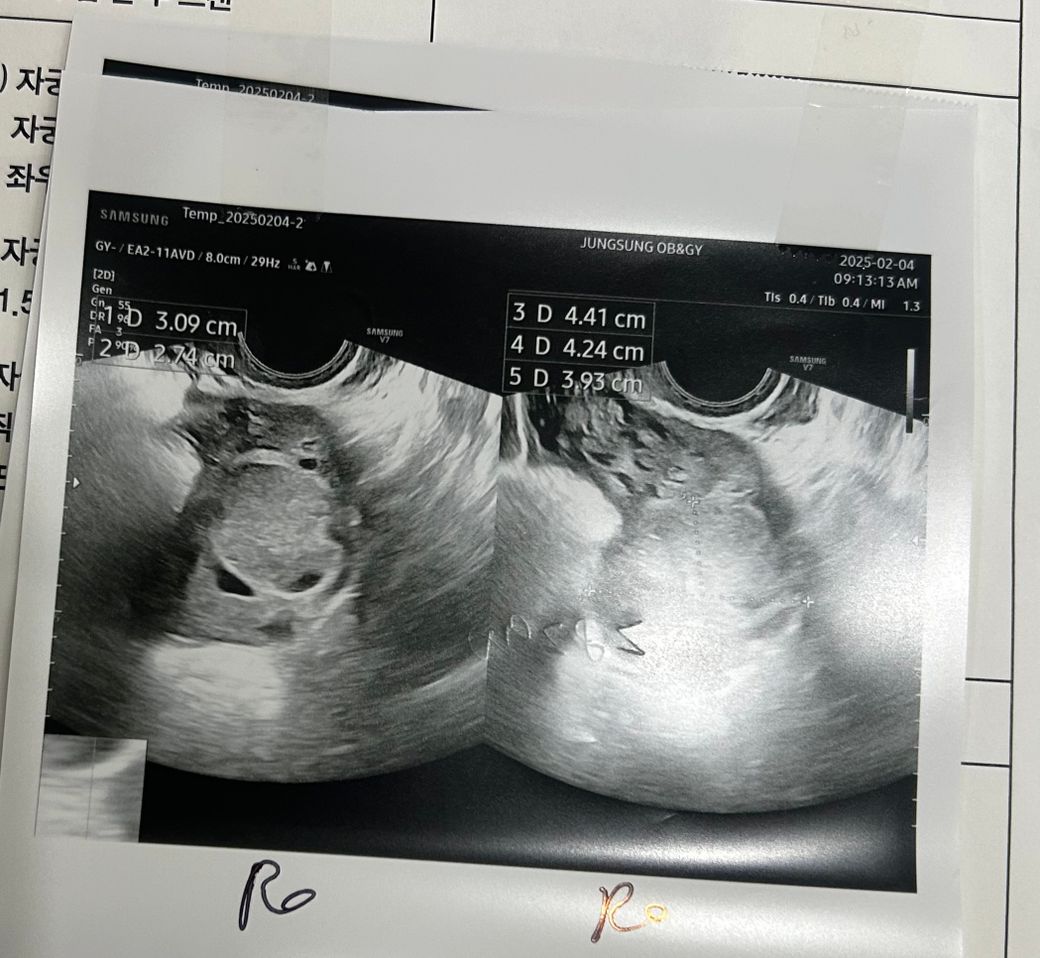

오른쪽 배가 너무 아파서 초음파를 했는데

단순 cyst 는 아니라하고 추적관찰하자고

하는데 뭘까요?

노란색원이 난소고 빨간색 원이 혹입니다.

• 1번 째 사진

• 2번 째 사진